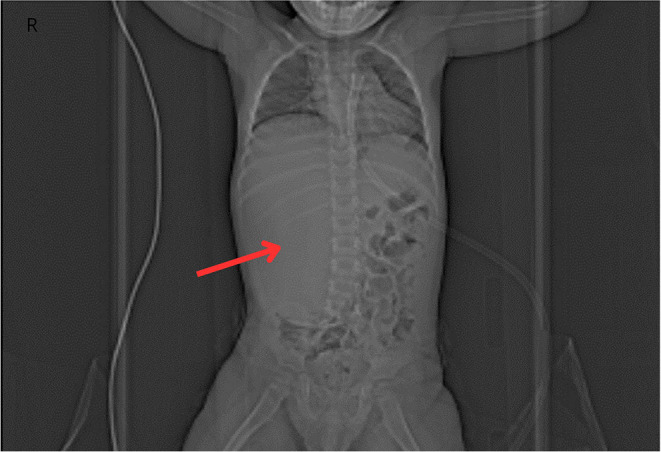

肾母细胞瘤(Wilms' tumor, WT)是儿童最常见的肾脏肿瘤。尽管它生长迅速,但它通常是无症状的。它最常见于3至5岁之间,在女孩中更为常见。大量研究报告了Wilms肿瘤的发生与遗传背景之间的联系。双侧肾母细胞瘤(BWT)的治疗提出了几个挑战。最近的研究提出了遗传对BWT发育的影响的问题。我们相信我们的病例报告是创新的,因为它提供了一种罕见的临床表现的信息,并全面地解决了遗传研究对有利治疗结果的潜在影响,这在文献中只进行了有限的详细讨论。病例描述涉及一名2岁和5个月大的患者,因腹部轮廓改变与其母亲一起就诊。在病史中,男孩的母亲曾接受过WT治疗。腹腔成像显示双肾存在病理性组织改变。在此基础上,诊断为V期Wilms肿瘤。男孩接受了右侧肿瘤肾切除术,随后左侧半肾切除术。他还接受了术前和术后化疗。基因检测显示WT1基因一个等位基因的外显子8和外显子9-10缺失。尽管对WT患儿的总体生存率数据乐观,但出现疾病复发和双侧BWT的患者仍存在一个重要的临床问题。这类患者通常需要根治性治疗,这将带来长期的后果。识别有家族性WT或BWT风险的患者允许相对早期的干预和有效的预防。此外,某些与WT相关的基因变异可以被认为是预后的生物标志物。

Wilms' tumor (WT) is the most common renal neoplasm in children. Despite its rapid growth, it is often asymptomatic. It most commonly occurs between the ages of 3 and 5, more frequently in girls. Numerous studies report an association between the occurrence of Wilms' tumor and genetic background. Treatment of bilateral Wilms' tumor (BWT) presents several challenges. Recent studies raise the issue of the influence of genetics on the development of BWT. We believe that our case report is innovative as it provides information on a rare clinical presentation and comprehensively addresses the potential impact of genetic studies on favorable treatment outcomes, which are discussed only in limited detail in the literature. The case description concerns a 2-year-old and a 5-month-old patient who presented with his mother due to a change in abdominal contour. In the medical history, the boy's mother had been treated for WT. Imaging of the abdominal cavity revealed the presence of pathological tissue changes in both kidneys. Based on this, stage V Wilms' tumor was diagnosed. The boy underwent a right-sided tumor nephrectomy followed by a left-sided heminephrectomy. He also received pre- and post-operative chemotherapy. Genetic testing revealed a deletion fragment of exon 8 and exons 9-10 on one allele of the WT1 gene. Despite optimistic data regarding overall survival in children with WT, a significant clinical issue remains with patients experiencing disease recurrence and bilateral BWT. Radical treatment is often required for such patients, which carries long-term consequences. Identifying patients at risk for familial WT or BWT allows for relatively early intervention and effective prevention. Furthermore, certain gene variants associated with WT can be considered prognostic biomarkers.